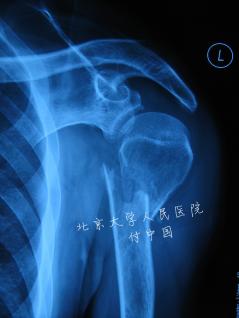

肱骨外科颈骨折